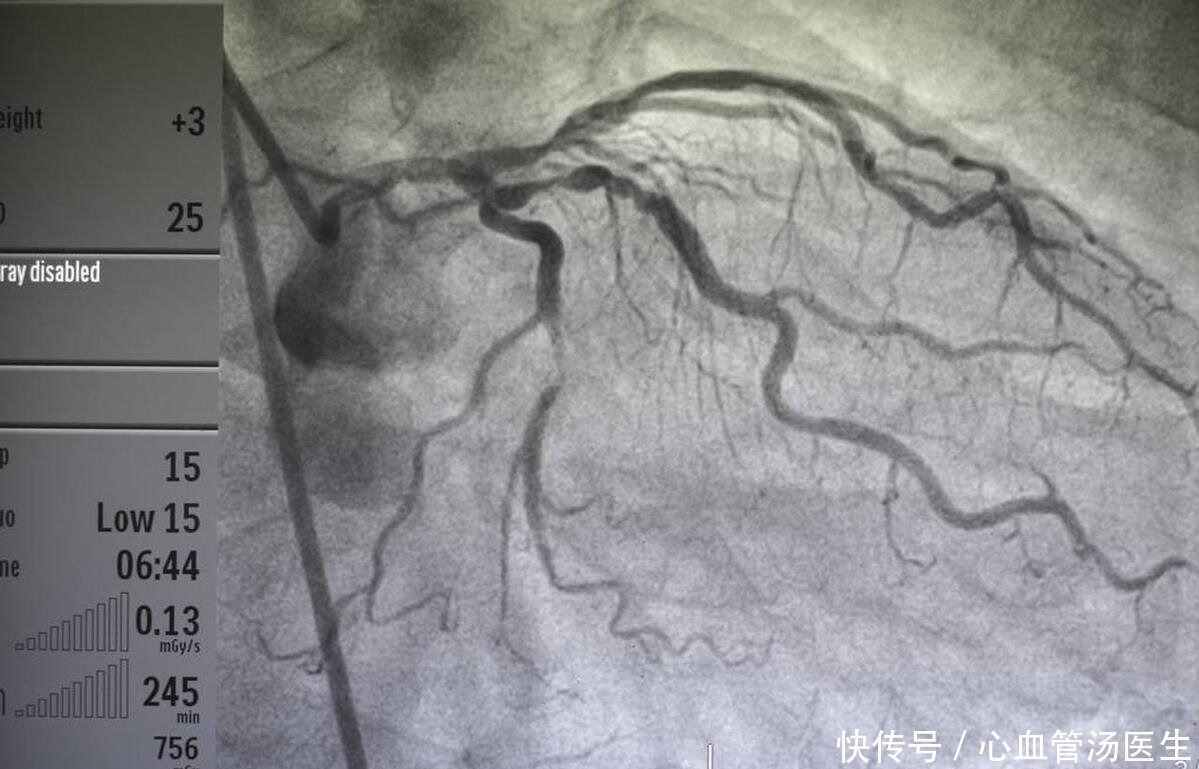

心血管病体检,为何要查那么多项目?直接冠脉造影好不好?